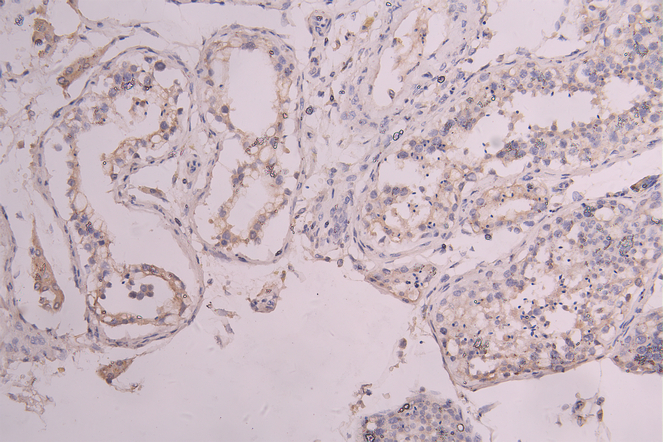

IHC image of CSB-RA012375MA1HU diluted at 1:100 and staining in paraffin-embedded human testis tissue performed on a Leica BondTM system. After dewaxing and hydration, antigen retrieval was mediated by high pressure in a citrate buffer (pH 6.0). Section was blocked with 10% normal goat serum 30min at RT. Then primary antibody (1% BSA) was incubated at 4°C overnight. The primary is detected by a Goat anti-human polymer IgG labeled by HRP and visualized using 0.05% DAB.